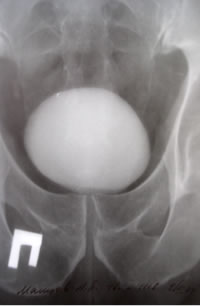

ОБСЛЕДОВАНИЕ

Рентгенологическое исследование

нижних мочевых путей (НМП)

урофлоуметрия